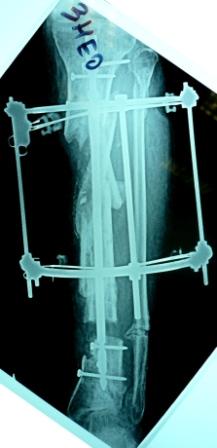

3) Третьим этапом наложили модуль на промежуточный фрагмент.(рис 3)  И начали его транспорт на стержне в проксимальном направлении. (рис 3 а)

Надеемся что <вырастет> регенерат в дистальном отделе, а в проксимальном отделе фрагмент <упрется> и прирастет.

Имя     : рис 3 а.JPG

Тип     : image/jpeg

Размер  : 16419 байтов

Описание: отсутствует

Url     : http://weborto.net:8080/pipermail/ortho/attachments/20090405/a3dc024e/attachment-0017.jpeg

Имя     : рис 3 а (1).JPG

Размер  : 16785 байтов